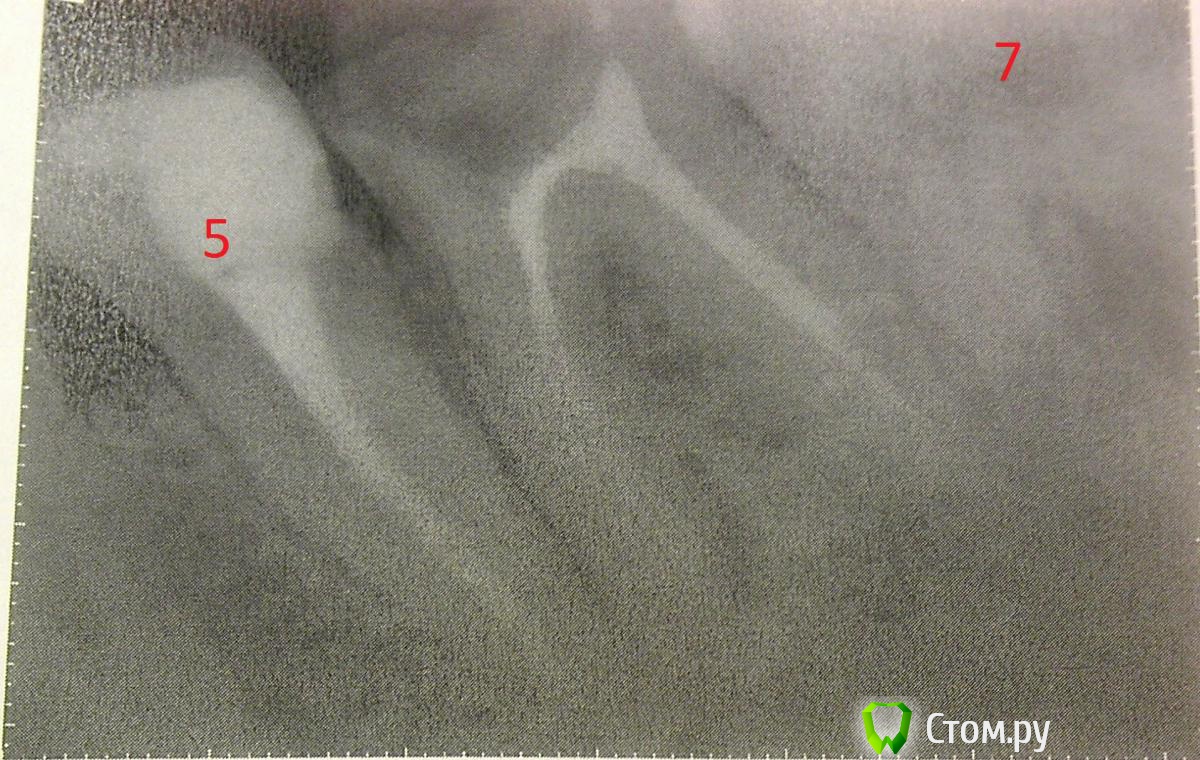

Зайка Опубликовано 20 марта, 2014 Поделиться Опубликовано 20 марта, 2014 Здравствуйте,хотела бы получить консультацию по поводу удаления восьмерок,нужно ли это делать?можно ли считать,что слева вверху ползет девятка?недавно ходила лечить зубы,десна сверху и снизу слева были немного припухши,в верхнем ряду между шестеркой и семеркой,стоматолог диагностировала карман,поэтому сняла пломбу с шестерки.Слева внизу был так же диагностирован карман,но между 5 и 6 зубом,так же была снята пломба.после снятия пломб отечность десен усилилась и десна стали очень сильно болеть,пью обезбаливающие и иногда ставлю кетонав.Стоматолог прописывала полоскания и гели,но так как у меня сахарный диабет 1 типа,гели мне не подходят,от полоскания спиртовыми растворами припухлость только усиливается,поэтому полощу лесным бальзамом с корой дуба,завариваю ромашку,а так же полощу хлоргекседином,но отечность так и не спадает.Сходила к пародонтологу,она сказала,что возможно дело в восьмерках и это они так болят,так как в целом десна выглядят неплохо и так болеть не должны.Из всех зубов мудрости чуть показалась только правая нижняя восьмерка,остальные все под десной.От пародонтолога получила направление к хирургу,консультация результатов не дала,так как врач сказал,что это не могут быть восьмерки.Справа в нижнем ряду семерка разрушина и подлежит восстановлению,есть ли смысл восстанавливать,пока там находится восьмерка?Так же прилагаю отдельные снимки верхней и нижней шестерки,так как в верхней шестерке есть подозрение на перелом в корне зуба,а в нижней шестерке воспаление в корне.Хотелось бы узнать Ваше мнение,в чем причина болей и воспаления десны и что с этим делать?нужно ли удалять восьмерки? Ссылка на комментарий

Bier Опубликовано 21 марта, 2014 Поделиться Опубликовано 21 марта, 2014 не поймешь есть ли там трещина. Скорее нет, чем да.Да, для восстановление 47з нужно удалить 48з. Ссылка на комментарий